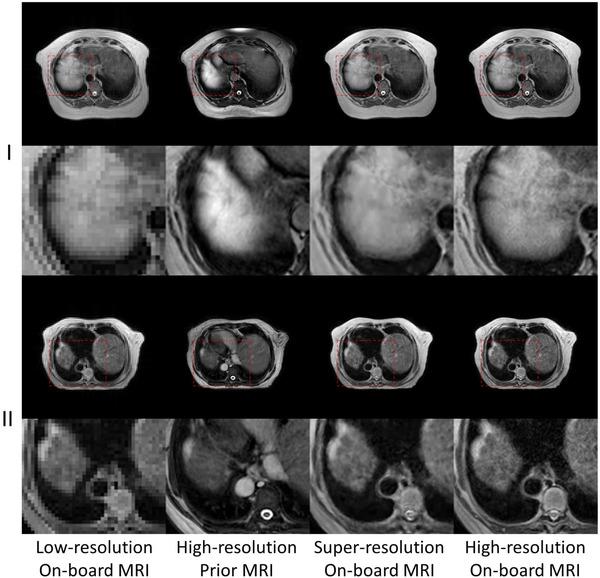

To achieve super-resolution for on-board MRI, this study proposed a universal anatomical mapping and patient-specific prior implicit neural representation (USINR) framework. Unlike traditional methods that interpolate solely based on individual on-board MR images, USINR can fully utilize the patient-specific anatomical information from a high-resolution prior MRI. In addition, USINR leverages knowledge about universal mapping between population-based prior MRIs and on-board MRIs, elevating the upper bound of super-resolution performance and enabling faster on-board fine-tuning.

USINR was evaluated on three datasets, including IXI, BraTS, and an in-house abdominal dataset. It achieved state-of-the-art performance on all of them. For example, on the BraTS dataset, USINR was trained on 1151 paired training samples (for universal anatomical mapping) and tested on 50 patients. It achieved average SSIM, PSNR, and LPIPS scores of 0.9656, 37.12, and 0.0214, respectively, significantly outperforming the published state-of-the-art method SuperFormer, whose corresponding scores were 0.9488, 35.83, and 0.0388. Furthermore, USINR can complete patient-specific training in less than one minute, rendering it a favorable solution in time-constrained ART workflows. In addition to large-scale dataset evaluations, a case study was conducted on an in-house patient at UT Southwestern Medical Center. This case study included two MRI scans (a prior scan for plan simulation and a new one for on-board imaging) from a single patient with a long interval between two scans, during which the tumor size underwent a significant change. Despite these substantial anatomical changes between prior and on-board imaging, USINR was able to accurately capture the change in tumor size, highlighting its robustness for clinical applications.

为实现机载MRI的超分辨率,本研究提出了一种通用解剖映射和患者特异性先验隐式神经表示(USINR)框架。与传统方法仅基于单个机载MR图像进行插值不同,USINR可以充分利用来自高分辨率先验MRI的患者特异性解剖信息。此外,USINR利用了基于人群的先验MRI与机载MRI之间通用映射的知识,提高了超分辨率性能的上限,并实现了更快的机载微调。

USINR在三个数据集上进行了评估,包括IXI、BraTS和一个内部腹部数据集。在所有这些数据集上,它都取得了领先的性能。例如,在BraTS数据集上,USINR在1151对训练样本(用于通用解剖映射)上进行训练,并在50名患者上进行测试。它分别实现了平均结构相似性指数(SSIM)、峰值信噪比(PSNR)和学习感知图像补丁相似度(LPIPS)分数为0.9656、37.12和0.0214,显著优于已发表的领先方法SuperFormer,其相应分数分别为0.9488、35.83和0.0388。此外,USINR可以在不到一分钟的时间内完成患者特异性训练,使其成为时间受限的ART工作流程中的理想解决方案。除了大规模数据集评估外,还在德克萨斯大学西南医学中心的一名内部患者身上进行了案例研究。该案例研究包括来自一名患者的两次MRI扫描(一次用于计划模拟的先验扫描和一次用于机载成像的新扫描),两次扫描之间间隔较长,在此期间肿瘤大小发生了显著变化。尽管先验成像和机载成像之间存在这些显著的解剖结构变化,USINR仍能够准确捕捉肿瘤大小的变化,突出了其在临床应用中的稳健性。